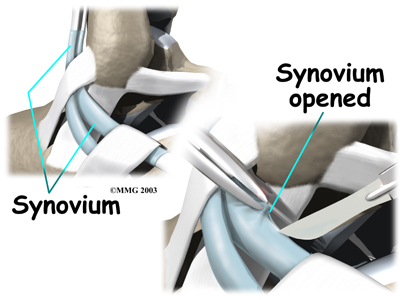

When the lining of the tendon is painful and inflamed (as in tenosynovitis), the goal of surgery is to remove the irritated tissue from around the tendon. This operation is called tendon release. This procedure is done by carefully dividing the tendon sheath that encloses the tendon. Once the , the surgeon around the tendon. The sheath is not stitched back together. The gap in the sheath will eventually fill in with scar tissue. The skin is closed with sutures.

Debridement

The procedure for surgically treating tendonosis is similar to the method used for tenosynovitis. However, extra measures are taken to thoroughly remove (debride) the degenerated tissue around and within the involved tendon.

Tendon Repair

Tendonosis may require repair if a preoneal tendon is split down its length. This type of tear mainly affects the peroneus brevis. The surgeon fixes this problem by first around the tendons. If the split is smaller than one-third the width of the tendon, the torn portion may simply be removed. Larger splits are sutured along the length of the tendon. The tendon sheath is , and the skin is closed with sutures.